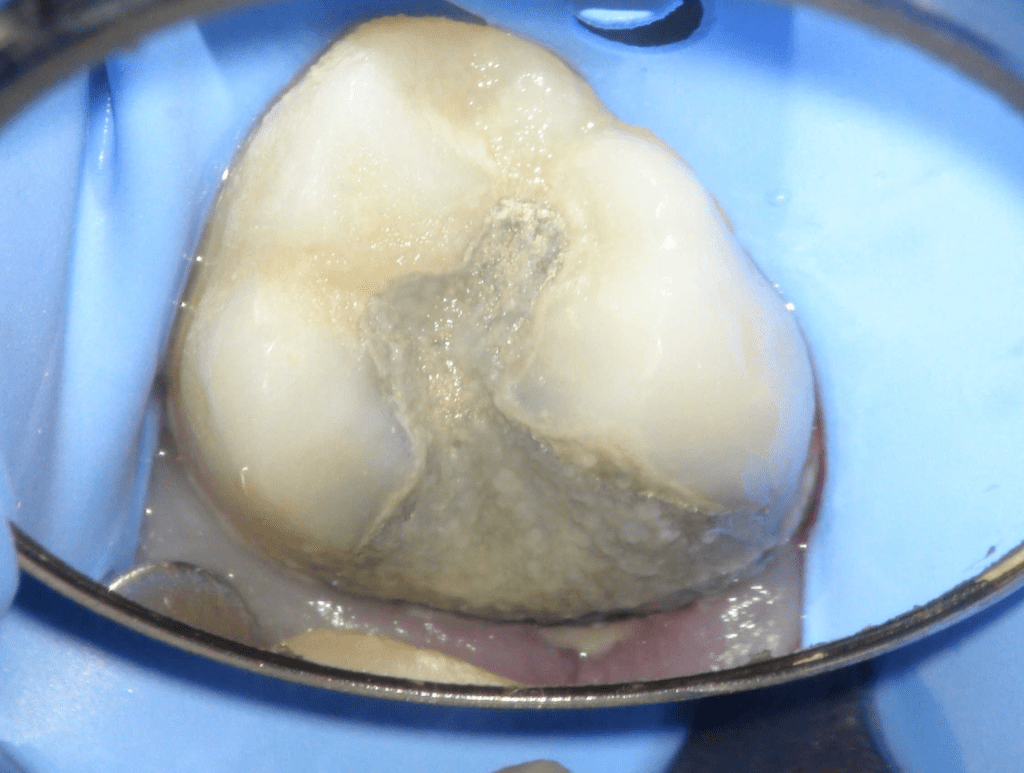

Fisura, remoción amalgama para explorar